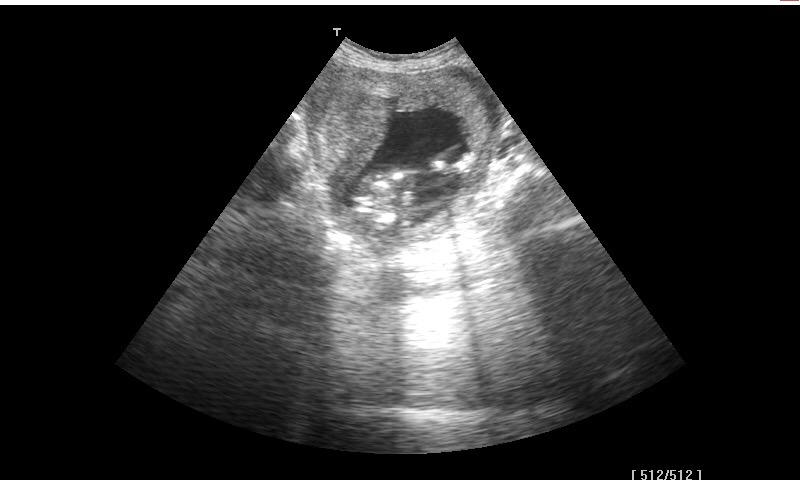

Is this a boy or a girl? Scan was taken with 17 weeksAttachment 35932

I would guess girl...feel like I see a "hamburger" in the first pic....I'm no expert though :)

Maybe girl but the pics arent clear anymore pics?